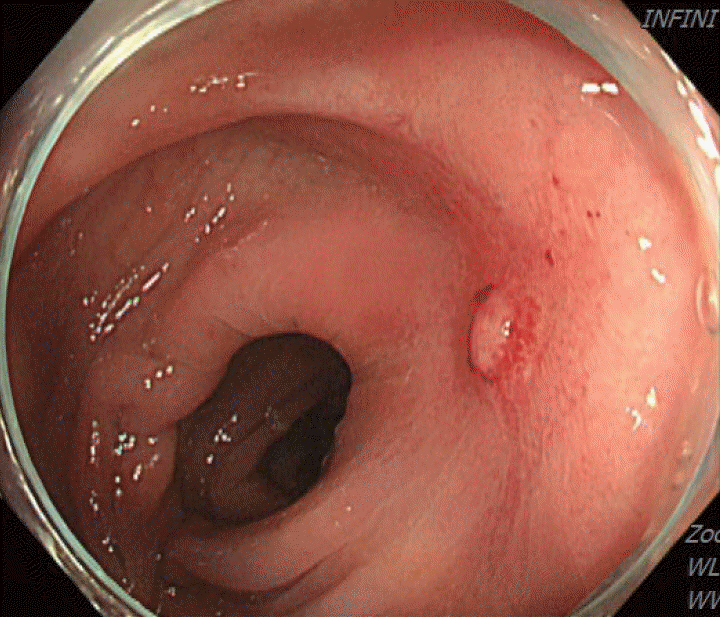

Figure 3.

Colonoscopy showing a scarred sigmoid ulcer 30 cm from the anal verge, with apparent improvement compared to previous findings.

A 70-year-old male underwent sigmoidoscopy after a routine computed tomography (CT) examination, which showed thickening of the sigmoid wall (Fig. 1). Sigmoidoscopy revealed a colonic ulcer, and a biopsy was performed. The lesion was identified as a tubular adenoma; therefore, the patient was referred to the gastroenterology department for repeat biopsy and additional tests. The patient’s medical history included high blood pressure and alcoholic hepatitis. His social history showed that he drank 0.5-1.0 bottle of soju daily and was never a smoker. Information regarding his family history was excluded from the study. The patient had no gastrointestinal symptoms such as abdominal pain or diarrhea, and physical examination findings were unremarkable. Although the biopsy showed a tubular adenoma, the initial colonoscopy indicated that the gross margin of the ulcer was irregularly shaped (Fig. 2), raising suspicion for malignancy. Therefore, despite being asymptomatic, the patient was informed, and another colonoscopy was performed 2 months later. The follow-up examination revealed a scarred sigmoid ulcer located 30 cm from the anal verge, which seemed to have improved compared with the previous findings. Re-biopsy demonstrated features consistent with a simple ulcer (Fig. 3). Accordingly, we concluded that this was a benign colonic ulcer with an inflammatory and ischemic cause rather than cancer, and a follow-up CT scan was sche-duled 1 month later. At the follow-up visit 1 month later, the patient complained of abdominal discomfort after eating for a week, which had not occurred before. He denied having fever, chills, nausea, or vomiting. A subsequent abdominal CT scan showed an approximately 9-cm cavitary lesion abutting the sigmoid colon and urinary bladder dome in the small intestine (Fig. 4). This was accompanied by diffuse nodular omentomesenteric infiltration and peritoneal thickening with small ascites. Based on these findings, the patient was suspected to have a malignant tumor, such as scirrhous carcinoma, inflammatory bowel disease, peritoneal carcinomatosis, or peritonitis, and was referred to a surgeon for surgical treatment. The patient was hospitalized immediately. On admission, the patient complained of abdominal discomfort after eating, and mild generalized abdominal tenderness was noted on physical examination. He was hemodynamically stable. Laboratory testing revealed high white blood cell count of 11.45 × 103/μL (normal range, 4.0-10.0 × 103/μL) with a differential of 67.6% neutrophils (normal range, 38.0-75.0), normal hemoglobin of 16.1 g/dL (normal range, 13.0-17.0), normal platelet count of 151 × 103/μL (normal range, 150-400 × 103/μL), and slightly elevated C-reactive protein level of 7.69 mg/L (normal range, 0.0-5.0). Serum electrolyte and kidney function test results were normal. On the 3rd day of hospitalization, the patient underwent laparoscopic small bowel resection. Immunohistochemical analysis of the resected tissue showed positive staining for CD3, CD4, CD8, CD56, and CAM 5.2 (epithelial marker), and a negative staining for CD10, CD20, CD21, and CD30 (Fig. 5). Histopathological evaluation revealed infiltration by small- to medium-sized T-cell with prominent epitheliotropism, consistent with MEITL. The final diagnosis was MEITL, involving the sigmoid colon, urinary bladder, and peritoneum. Postoperatively, the patient developed persistent ileus with progressive ab-dominal distension and loss of bowel passage, necessitating a second emergency surgery on the 20th day of hospitalization. On the 25th day of hospitalization, the Hemovac drainage became purulent, blood pressure decreased, and the patient went into shock; therefore, a third emergency surgery was performed under the suspicion of bowel perforation. On the 45th day of hospitalization, the patient died of refractory septic shock, presumed to be a complication of intestinal perforation.

MEITL manifests as a wide variety of gastrointestinal symptoms, ranging from abdominal pain, weight loss, and diarrhea to serious symptoms such as bleeding, perforation, and obstruction; however, no characteristic clinical symptoms have been established for this disease [6]. Only 10% of affected patients are diagnosed endoscopically, with majority diagnosed through surgery [7]. As in the present case, MEITL is often discovered accidentally without symptoms or is diagnosed when the disease has already progressed [4]. Among few papers presenting the endoscopic findings of MEITL, Tian et al [8]. described this disease as a semicircular shallow ulcer accompanied by numerous fine granules and mucosal thickening. In our patient, ulceration with associated mucosal thickening was also observed. Histomorphologically, neoplastic cells in MEITL are described as small- to medium-sized, monomorphic, and epitheliotropic lymphocytes, with pale cytoplasm and round nuclei [2]. The cells are CD3+, CD4-, CD5-, CD8+, CD56+, CD30-, MATK+, EBER-, and T-cell receptor-gamma delta+ [9]. Cytotoxic markers such as TIA-1, granzyme B, and perforin are also present [9]. Cyclophosphamide-adriamycin-vincristine-prednisone-based chemotherapy, with or without consolidative autologous stem cell transplantation, remains the mainstay of treatment [3]. In an Asian MEITL series, 72% of patients were treated with chemotherapy, whereas 58% underwent both surgery and chemotherapy [5]. However, the high rate of treatment discontinuation owing to disease progression or treatment-related adverse events continues to be a major concern in this patient population [1]. Surgical resection is necessary when symptoms appear, and approximately 50% of patients undergo emergency surgery for intestinal perforation or obstruction [5,7]. If intestinal perforation occurs, the prognosis is expected to be worse, as chemotherapy is delayed owing to peritonitis, septic shock, and multiple organ failure [10]. In the present case, treatment was likely delayed because of intestinal obstruction prior to anticancer therapy, leading to rapid clinical deterioration. Generally, the diagnostic ratio of intestinal T-cell lymphoma (ITCL) by endoscopy, including tissue biopsy, is low [11] for the following reasons: 1) tissue specimens from endoscopic biopsy are usually not sufficiently large to allow a correct diagnosis; 2) ITCL is primarily located in the submucosa and smooth muscle, and detection of the lesion through the mucosal layer from biopsy specimens is difficult; and 3) the disease can easily be overlooked because of its rarity. Therefore, tissue biopsies of ulcerative gastrointestinal lesions should be performed carefully from the base of the ulcer while considering the possibility of malignant lymphoma [11]. In this patient, despite a prompt biopsy following the incidental detection of a colonic ulcer and a second endoscopic biopsy performed shortly thereafter, an endoscopic diagnosis could not be achieved. If several deeper biopsies, including those of the submucosa, were performed at the time of the initial endoscopy, the possibility of early diagnosis may have increased. Moreover, although our patient underwent colonoscopy over a short follow-up period, the ulcer showed an atypical clinical course, appearing to improve and form a scar within a short interval. Such a presentation has rarely been reported in the related literature, and we report this case to highlight its unusual endoscopic features. Additionally, owing to this atypical pattern, careful differen-tiation from other diseases, such as benign ulcers or inflammatory bowel disease, is necessary. Our case underscores the importance of early diagnosis of MEITL, as the rapid progression of the disease can have a fatal consequence. Endoscopists and clinicians need to be vigilant in understanding endoscopic and histological findings to ensure prompt diagnosis and treatment of this aggressive disease.